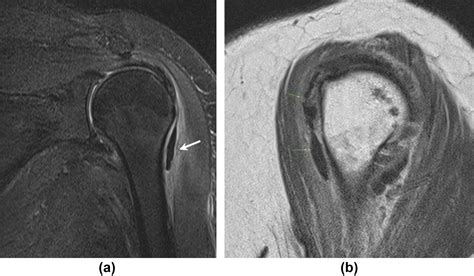

MRI Rarely needed, but used if doctors need to rule out rotator cuff tears or other structural damage.